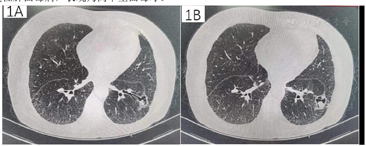

就诊时胸部CT平扫示左肺下叶霉菌球及气囊,肺间质纤维化,双肺多发小结节。结合气管镜肺泡灌洗液NGS及协和医院病理会诊明确诊断慢性肺曲霉病。

患者复查胸部CT示病灶较前缩小。

经胸腔镜手术术后病理、术后气管镜NGS检测,明确诊断肺曲霉病。结合我院入院时影像,新月征显著,经1年余伏立康唑规范口服抗真菌治疗,于我院就诊时病情稳定,明确为慢性肺曲霉病,表现为简单型曲霉球。

分别于2021年12月30日、2022年1月6日、2022年1月17日、2022年1月25日行4次支气管镜检查及治疗,超声探查示左下叶前基底段外侧支异常低回声,局部予乙酰半胱氨酸+生理盐水反复灌洗后,注射猪源纤维蛋白粘合剂+两性霉素B,术后咳嗽症状缓解出院。2022年3月11日于我院通州院区住院,3月12日胸部CT平扫(经支气管镜局部注药后复查),曲菌球较我院初诊缩小(图2)。于2022年3月21日行经皮穿刺注药(猪源纤维蛋白+两性霉素B),复查即刻CT示气胸,予胸腔闭式引流(图3)。2022年3月23日行微波消融治疗(图4),45 W消融3 min,复查CT示覆盖病灶,继续保留闭式引流,次日复查胸片无气胸,拔除引流管。

患者复查胸部CT示病灶较前缩小(图5)。